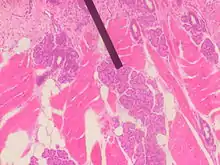

Glanda lui Ebner.